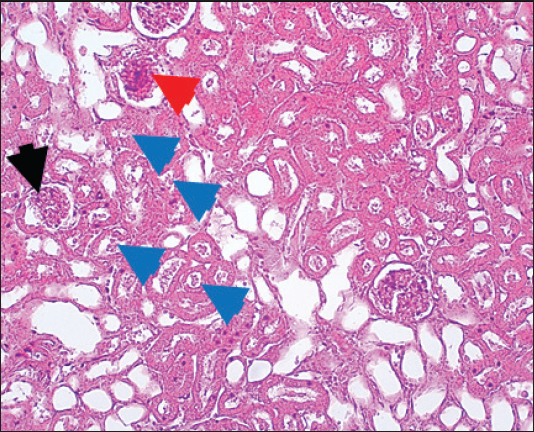

In the control group, histological analysis of kidney sections revealed intact glomeruli and renal tubules (Fig. 1). Conversely, Figure 2 presents a kidney section from the green tea group, which exhibited normal renal tubular epithelial cells, a well-preserved tubular lumen, and an overall normal tubular texture, although some glomeruli showed mild atrophy. The renal section of gentamicin showed atrophy of the glomerular tuft, expansion of the globular space, and significant hyperemia lesions in some glomeruli associated with substantial damage to the superficial cell layer (epithelial cells) in the proximal renal tubules, resulting in a reduction of the tubular lumen space (Fig. 3). In contrast, kidney sections from the gentamicin group that received green tea treatment revealed a marked reveal of both glomeruli and renal tubular epithelium, which appeared normal (Fig. 4 and Fig. 5).

Fig. 5. Kidney of protective group. The section shows normal renal tubular epithelial cells with a normal tubular lumen (Black arrows). A normal tubular texture with mild atrophy can be seen in some glomeruli (Blue arrow). H and E (10X).